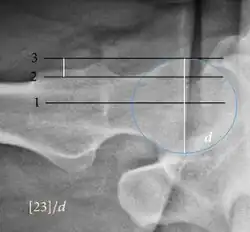

| Caput-sourcil angle[21] |

|

Superior to the Tönnis angle in cases without joint space narrowing or subluxation.[21] The medial point of the sourcil is at the same height as the most superior point of caput femoris. | −6 to 12°[21]